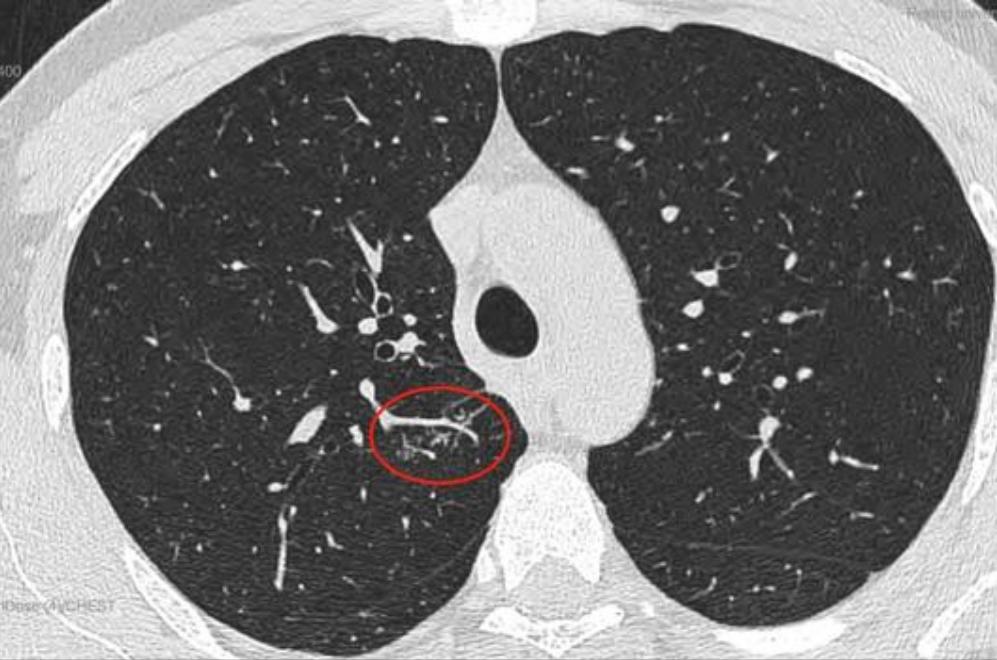

这是11月15日的CT图像与上次(7月29日)CT图像对比图:

再发一张:

辛苦主任,您看一下,结节虽然缩小了,还有1.7*0.9 CM,其他俩肺叶还有陈旧性病灶,应该继续服用拜复乐和夏枯草吗?8月份查过:男性肿标9项、过敏源检测(总IgE)、鳞状上皮细胞癌相关抗原、GM试验、隐球菌抗原、1,3-β-D葡聚糖 都是阴性,在正常范围内。就是结核感染T细胞还没查,您看是否需要查一下?主任辛苦您了,谢谢您!